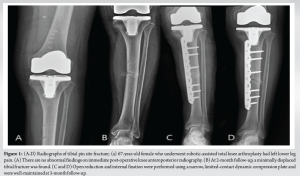

A 67-year-old female presented with bilateral knee pain for the past 4 years due to severe OA with a varus deformity. She had difficulty walking and climbing stairs because of the pain. The patient showed no improvement with conservative treatment or injections, and her activities of daily living were deteriorating. Her weight, height, and body mass index (BMI) were 47 kg, 150 cm, and 20.8, respectively. She underwent staged bilateral total knee arthroplasty using the CUVIS-Joint Robotic System (CUREXO Inc.). Four 3.2 mm diameter pins were used to place tracker arrays with two pins each for the femoral and tibial diaphysis. For the tibia, the first pin was placed 10 cm below the joint line, perpendicular to the anteromedial surface, and the second pin was placed through the drill guide provided with the system. Both were placed with separate stab incisions. For the femur, the first pin was placed 10 cm above the joint line, and the second pin was placed through the drill guide with a separate stab incision. Post-operative radiographs were normal with good alignment of the components. In the post-operative period, she was allowed immediate weight-bearing as tolerated and underwent normal physiotherapy as per our institutional protocol without the need for aggressive rehabilitation or manipulation. The patient was discharged without complications. At the 2-month follow-up, she reported aggravated pain in the left lower leg. Physical examination revealed swelling and tenderness in the mid-third of the left lower leg, with abnormal mobility and crepitus. Radiography revealed a transverse fracture of the left tibia at the distal pin tract site. The patient underwent open reduction and internal fixation with a narrow, limited contact dynamic compression plate (LC-DCP). During the post-operative period, the patient was kept non-weight-bearing for 6 weeks with quadriceps strengthening and knee range of motion (ROM) exercises. Partial weight-bearing was started after 6 weeks, with follow-up radiographs showing the progress of fracture union. After 3 months, bony union was identified, and the patient resumed her activities. The patient had full knee ROM at the final follow-up (Fig. 1a, b, c, d).